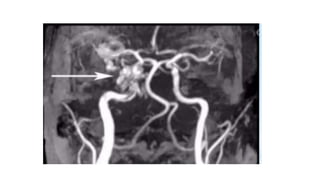

Radiographic features

• CT:

-Proptosis Enlarged superior ophthalmic veins

-Extraocular muscles may be enlarged

-Orbital oedema

-May show SAH/ICH from a ruptured cortical vein

Radiographic features • CT: -ProptosisEnlarged superior ophthalmic veins -Extraocular muscles may be enlarged -Orbital oedema -May show SAH/ICH from a ruptured cortical vein • Angiography (DSA) -Rapid shunting from ICA to CS -Enlarged draining veins -Retrograde flow from CS, most commonly into the ophthalmic veins • Ultrasound Arterialised ophthalmic veins may be seen on Doppler study